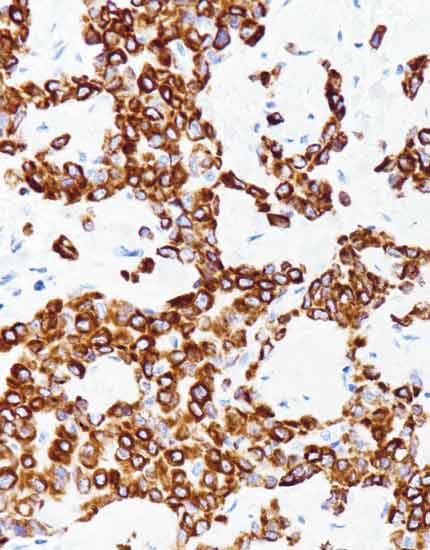

产品名称:CK5

产品编号:RMA-1064

阳性部位:胞质

图片描述:

恶性上皮样间皮瘤,CK5染色,细胞质阳性